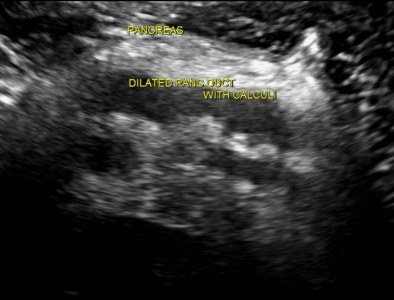

Расширенный проток поджелудочной железы на УЗИ

Внутренний диаметр нормального панкреатического протока менее 3 мм. Проток лучше визуализируется при поперечном сканировании в средней трети тела поджелудочной железы. Для того чтобы убедиться, что вы обнаружили именно проток, необходимо увидеть ткань поджелудочной железы с обеих сторон от него. Селезеночная вена сзади или стенка желудка спереди могут быть ложно интерпретированы как панкреатический проток.

Стенки протока поджелудочной железы должны быть гладкими, а просвет чистым. Когда проток расширен, стенки становятся неровными; сканируйте не только головку поджелудочной железы, но также и весь билиарный тракт.

Основные причины расширения панкреатического протока: опухоль головки поджелудочной железы или ампулы фатерова соска (сочетаются с желтухой и дилатацией билиарного тракта); камни общего желчного или панкреатического протока; хронический панкреатит; послеоперационные спайки.